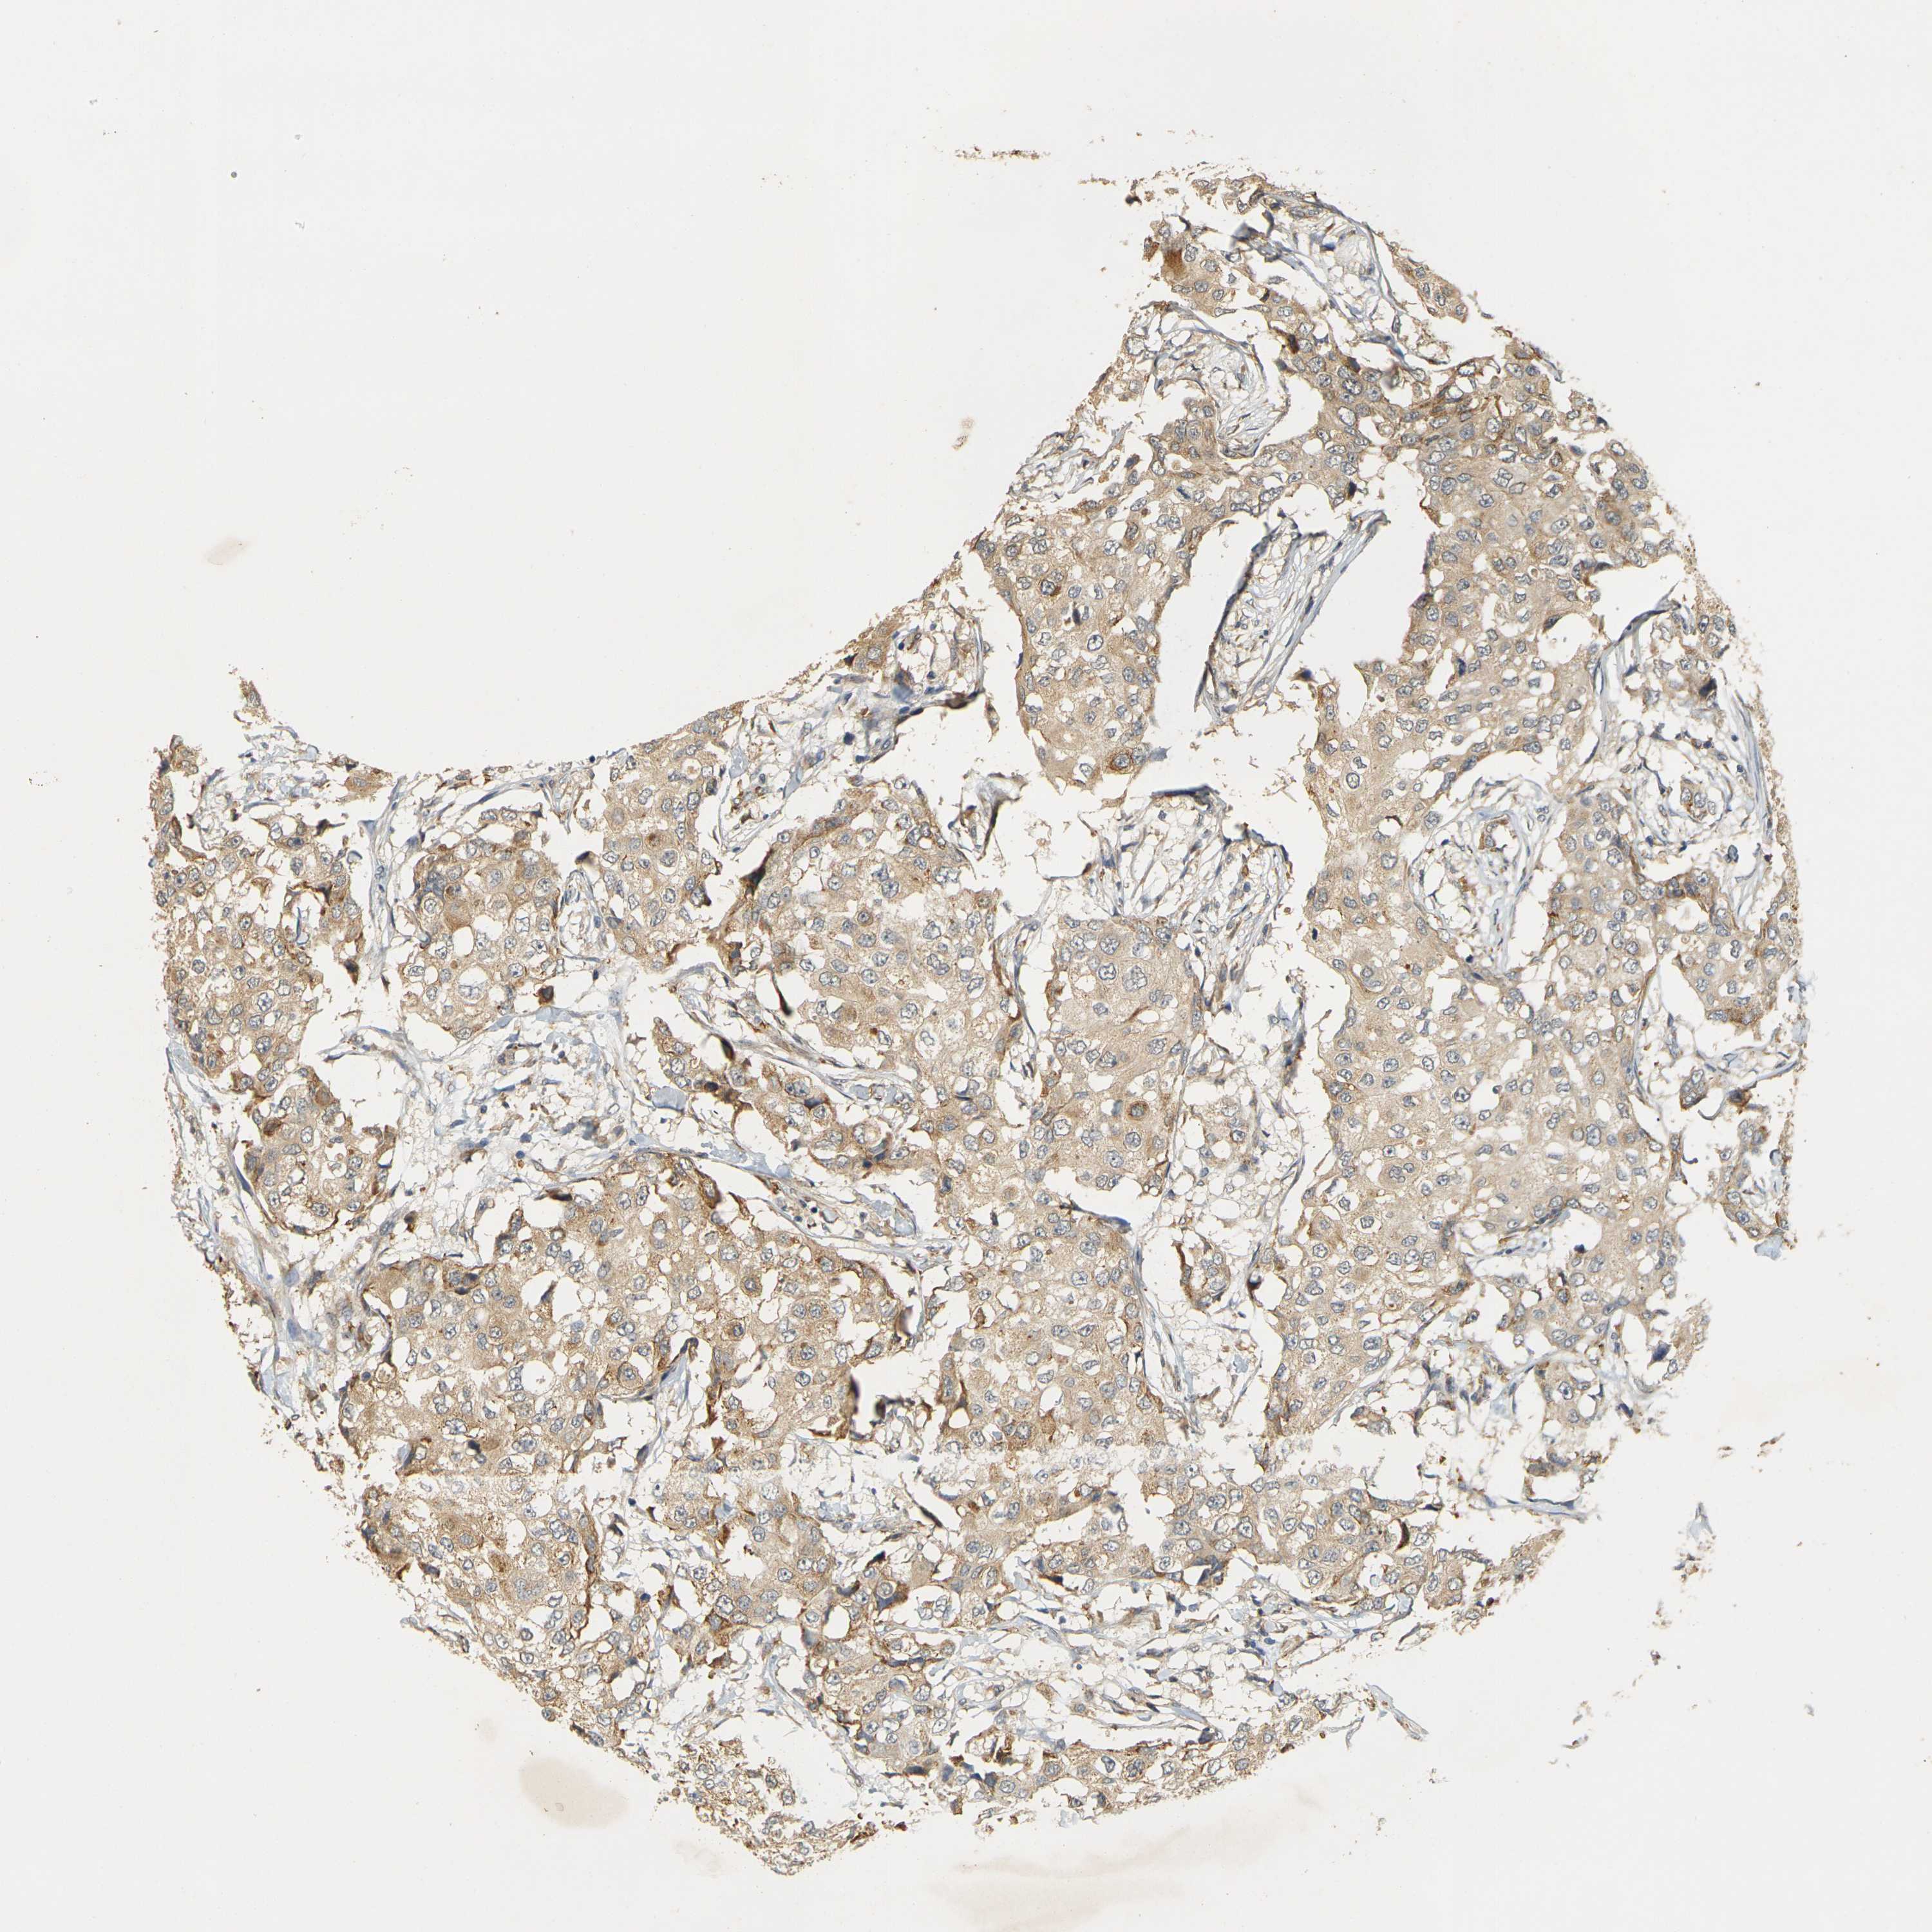

CANCER BREAST CANCER Show tissue menu

BRCA TCGA BRCA VALIDATION PROTEIN EXPRESSION